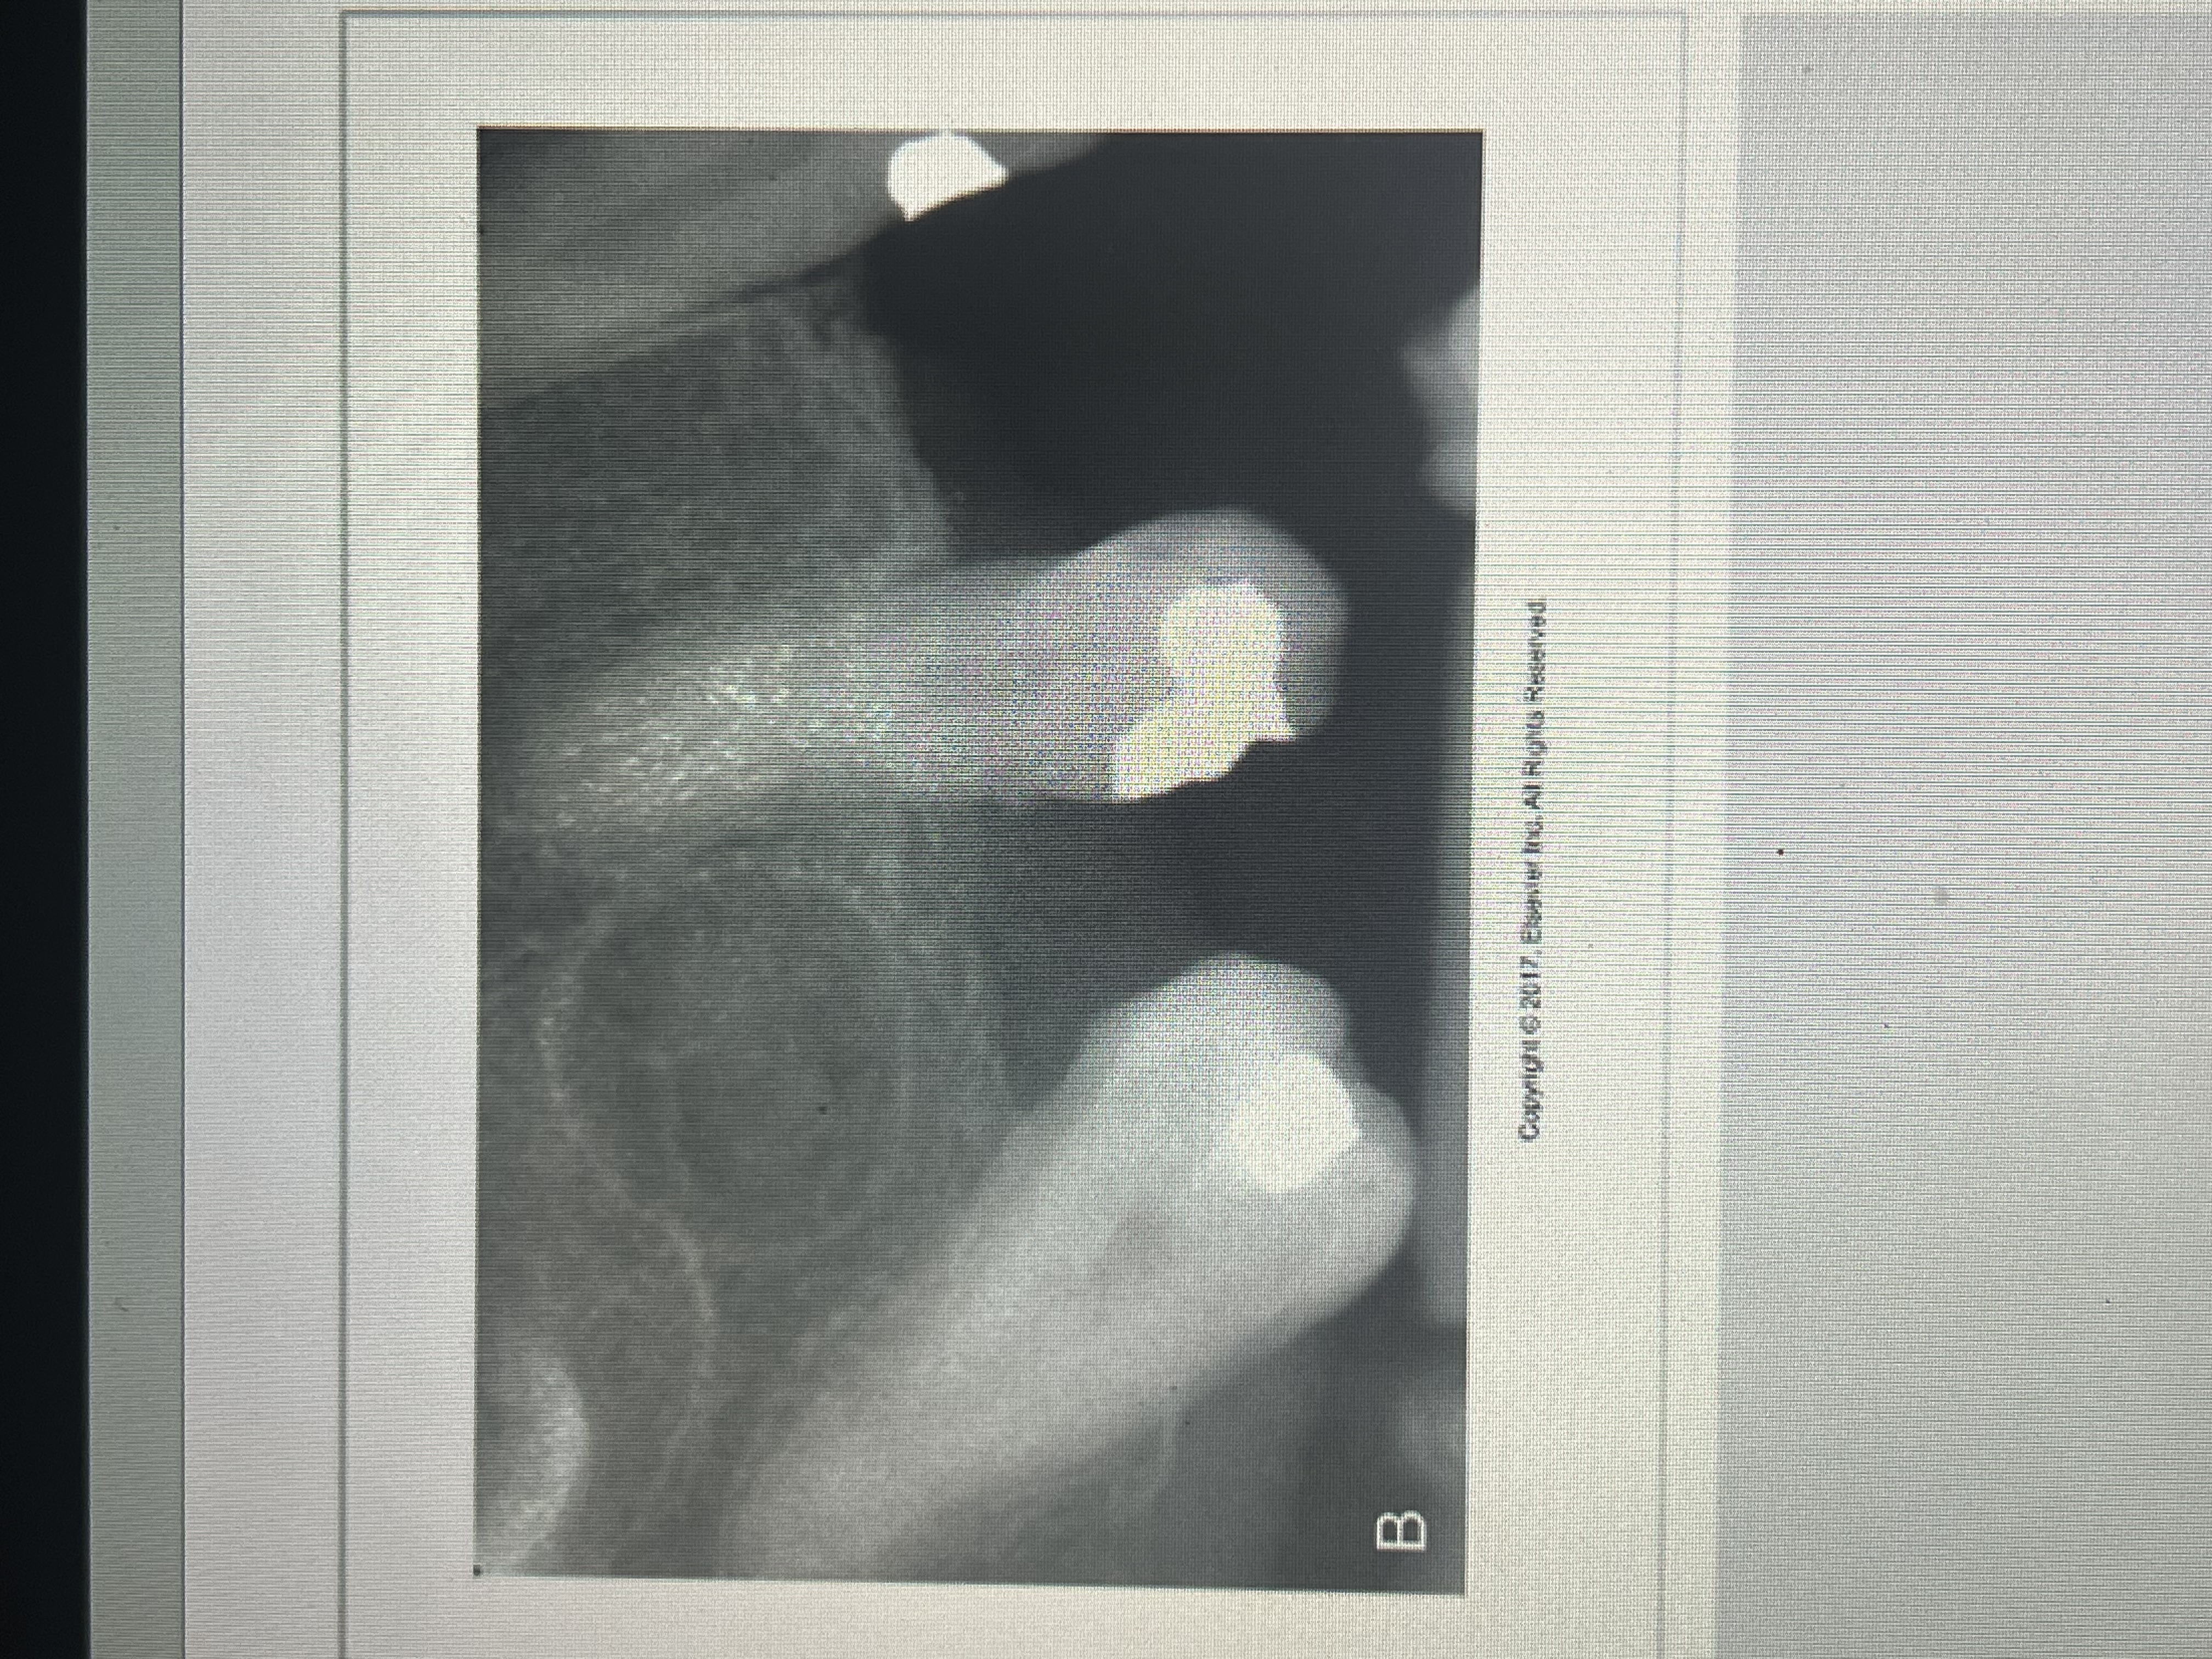

How do metallic restorations appear on a dental image?

completely radiopaque

How does amalgam appear on a dental image?

What does a gold restoration look like on a dental image?

A large radiopaque restoration with SMOOTH borders.

Large radiopaque restorations with smooth contours and regular borders. #18 and 19.